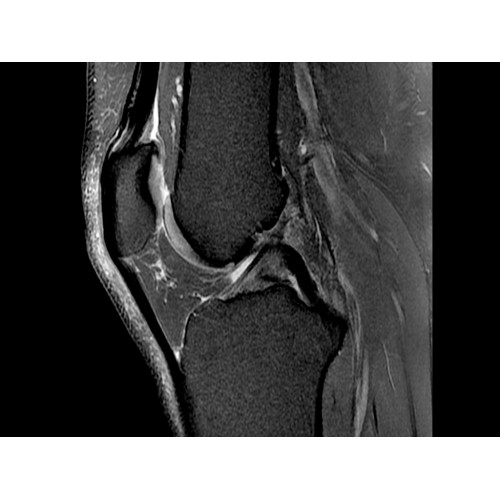

МРТ аппарат GE Optima MR450w 1.5T

МР-томограф с широким туннелем Optima MR450w является настоящей рабочей лошадкой и может эффективно обслуживать большее число пациентов. Томограф обеспечивает одновременно удобство пациента, продуктивность работы, отличное качество изображения. В этой МРТ-системе инженерам компании удалось без компромиссов совместить необходимый объем перемещения с удивительно высоким качеством изображения.

Благодаря принципиально новым технологиям мы расширили возможности МР-томографов с широкими туннелями, совместив непревзойденное качество изображений с высокой производительностью при широком — 50 см — поле зрения.

МР-томограф Optima MR450w позволяет получать изображения исключительно высокого качества, которые помогают установить диагноз. Чтобы удовлетворить ожидания клиентов в отношении высокого качества, в МР-томографе Optima MR450w были сохранены дополнительные возможности платформы Discoverу, привнесшие в его работу универсальность и мощь.

• РЧ-катушки, оптимизированные для исследования конкретных участков тела — элементы катушек высокой плотности располагаются вокруг исследуемых участков тела и при необходимости обеспечивают расширенный охват и оптимальное качество изображений при каждой процедуре.